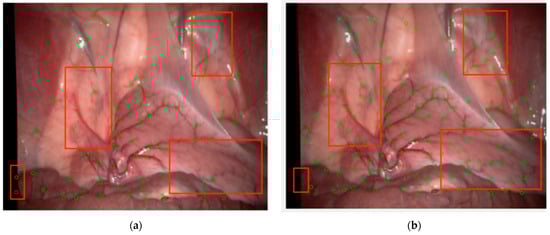

Objectively speaking, based on the feature point neighborhood block matching algorithm in PTAM, ZSSD is calculated for feature matching Experiments are conducted on base images from five data sets and a random image. For a comprehensive evaluation, the number of branch point extracts, repeatability, average error, and variance are used as evaluation indicators. Repeatability is the percentage of points detected in images from different viewpoints. The average error is the average mean of all matching points. Variance represents the distribution of feature points, and the larger the variance, the wider the distribution range. The results are shown in Table 3 compared with the method proposed in this paper and RBCT and the adaptive FAST (AFAST) algorithm by Liu et al. [42]. The matching effect is shown in clip3 and clip4 as examples, as shown in Figure 11. The above results indicate that the method proposed in this paper has significantly improved the number of extracted branch points, repeatability, and variance compared to the original method, and the average error has generally decreased.

Figure 11.

Illustration of matching vascular branching points: (a) clip3 (Vivo data set); (b) clip4 (Vivo data set).